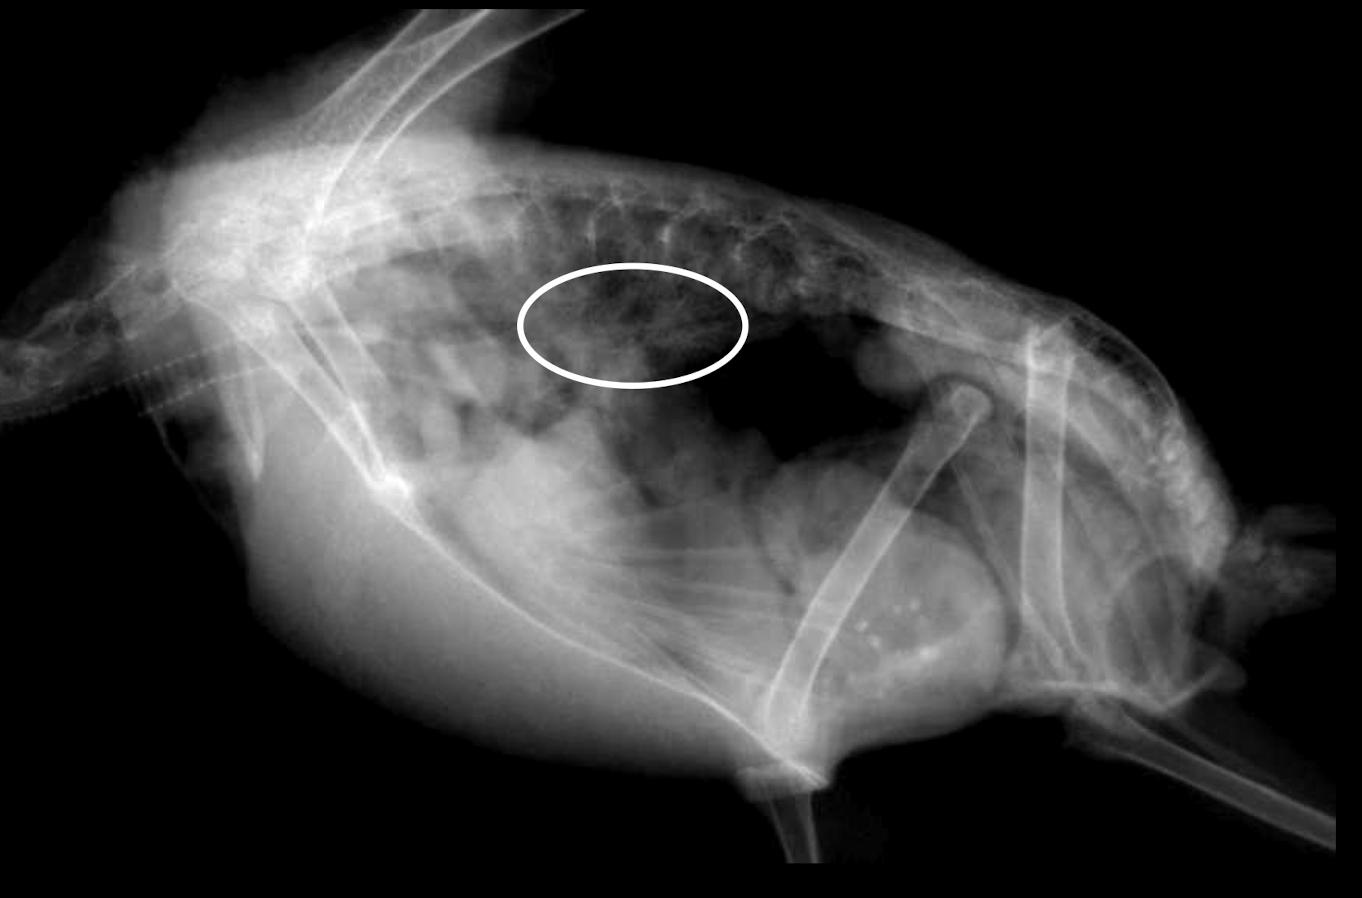

Whats wrong?

Bacterial airsacculitis → thickening of airsac wall